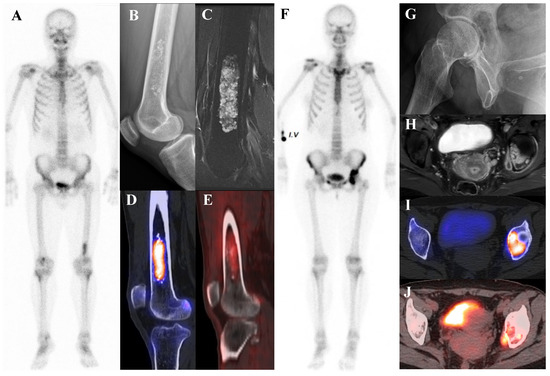

Current Position of Nuclear Medicine Imaging in Primary Bone Tumors

Primary bone tumors encompass a heterogeneous spectrum ranging from benign entities to highly aggressive sarcomas. This review aims to summarize the current role and future perspectives of nuclear medicine in the diagnosis, staging, and management of primary bone tumors. Accurate diagnosis and staging [...] Read more.

Primary bone tumors encompass a heterogeneous spectrum ranging from benign entities to highly aggressive sarcomas. This review aims to summarize the current role and future perspectives of nuclear medicine in the diagnosis, staging, and management of primary bone tumors. Accurate diagnosis and staging are critical yet challenging due to histologic heterogeneity and overlapping imaging features. While radiographs, computed tomography (CT), and magnetic resonance imaging (MRI) remain essential, nuclear medicine provides a complementary functional perspective by assessing bone turnover, vascularity, and glucose metabolism. Bone scintigraphy is highly sensitive for skeletal lesions and useful for detecting skip lesions or multifocal disease, although its specificity is limited. Hybrid single-photon emission computed tomography (SPECT)/CT enhances diagnostic confidence through precise anatomic localization and quantitation. [18F]fluorodeoxyglucose ([18F]FDG) positron emission tomography (PET)/CT, by directly visualizing tumor metabolism, has become a cornerstone in osteosarcoma and Ewing sarcoma management, demonstrating superiority over bone scintigraphy for detecting skeletal metastases. In chondrosarcoma, [18F]FDG uptake correlates with histologic grade, although overlap with benign cartilage tumors complicates interpretation. Future directions include the integration of quantitative SPECT, artificial intelligence, and novel tracers such as [18F]sodium fluoride and [68Ga]Ga-fibroblast activation protein inhibitor (FAPI). Collectively, nuclear medicine imaging is becoming a key element in musculoskeletal oncology, offering unique biological insights that complement anatomic imaging and contribute to improved patient management. Full article

Show Figures

Figure 1